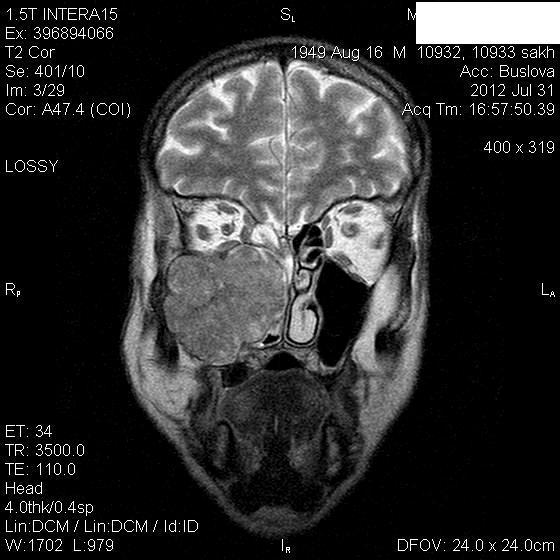

Мужчина лечился около месяца от правостороннего гайморита.Неоднократно пунктировали.Выписался из стационара, через 3 дня попал к другому ЛОР-врачу, который направил пациента на КТ, но волею судеб он оказался у нас.Визуально: незначительный экзофтальм справа, отек скуловой области, который периодически исчезает.Пыталась добыть его рентгеновский снимок пазух через знакомого отоларинголога, вхожего в лечебное учреждение, где лечился пациент-бесперспективно ( просто исчез, со слов лечащего врача-обычный правосторонний гайморит), хотя просила всего-то для себя, чтобы самой в такую ситуацию не попасть.

В заключение выставила объем.

Где-то в душе грелась мысль о нагноившейся гематоме, пока не показала исследование нашему отоларингологу, который пытался помочь в поиске рентгенограммы.

Нашла похожее образование в книге Г.Труфанова как плоскоклеточный рак.

Вот буквально две недели назад у нас был почти аналогичный пациент , он тоже длительно ходил по врачам и лечился прогреваниями от стреляющих в висок болей. Пришел на МРТ случайно -отправила к ЛОР и челюстно-лицевым хирургам. Думаю и здесь есть озлокачествление хронического процесса. Трудно сказать есть ли деструкция медиальной стенки пазухи , деформация точно есть.